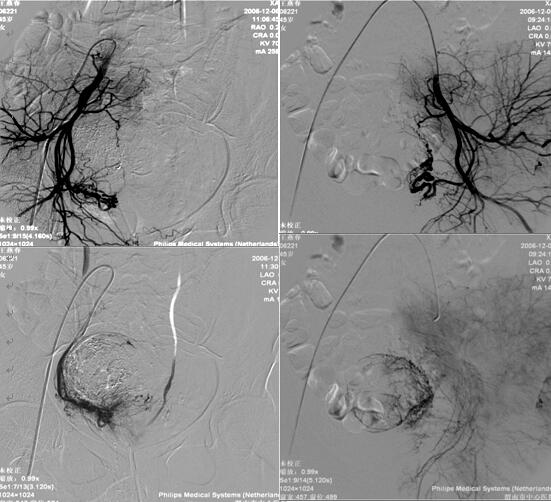

渭南市中心医院介入科在李建国主任带领下自2006年开展子宫肌瘤栓塞术,现已完成数百例相关疾病介入治疗,为渭南地区及各县患者提供了全新的子宫肌瘤治疗方法,避免患者子宫全切。子宫肌瘤栓塞术是一种安全有效的治疗方法,是由介入医生经病人腹股沟股动脉导入一导管至肌瘤的血供(子宫动脉)处,释放一些细微颗粒,弹簧圈、或者球囊等阻断肌瘤的血供、供养及出血部位,使肌瘤纤维化,出血停止,肌瘤萎缩。所有经过介入治疗的患者术后大约3-6个月相关症状完全消失。

经子宫动脉栓塞术还可应用于子宫腺肌症、胎盘植入、瘢痕妊娠、前置胎盘及产后大出血等疾病,以下为一例产后大出血患者介入治疗图片: